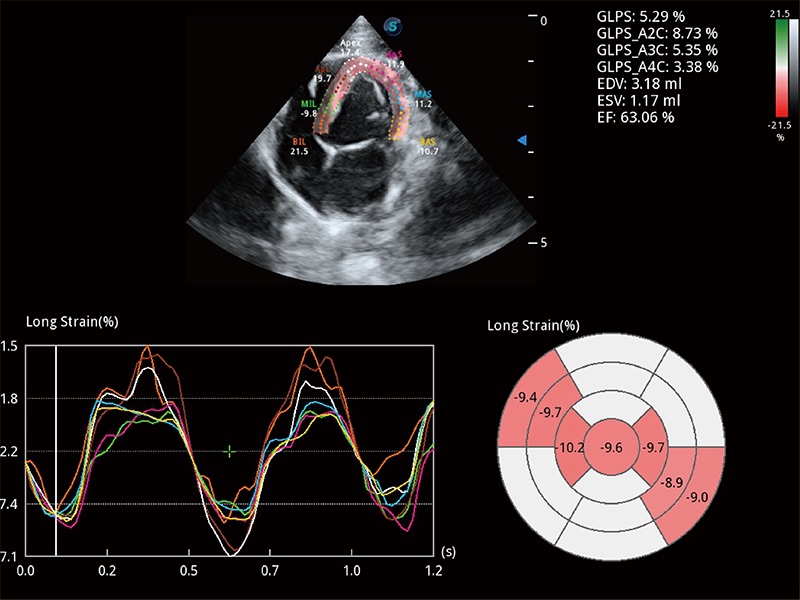

通過心肌識別技術(shù)與二維斑點(diǎn)追蹤技術(shù)相結(jié)合,對心臟的超聲圖像進(jìn)行量化分析。計算心肌17個節(jié)段的應(yīng)變、應(yīng)變率、速度、位移等,并通過牛眼圖的形式進(jìn)行呈現(xiàn)。

能夠基于左心室壁追蹤和辛普森法,自動計算射血分?jǐn)?shù),支持多個可移動點(diǎn)描跡,與手動測量相比,極大節(jié)省了動物醫(yī)生的時間和精力。